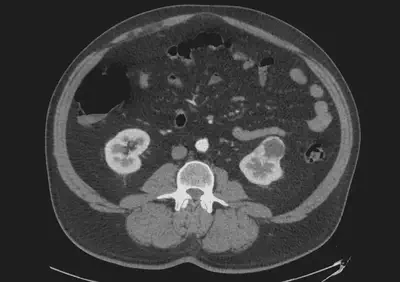

Despite advances in medical imaging over the past few decades, it cannot accurately determine whether a small (<4 cm) renal mass is benign or malignant. This makes it difficult for urologists to select patients who would benefit from a conservative approach (active surveillance) rather than invasive treatment. Currently, the treatments available are: (1) surgery and (2) thermoablation. Despite their effectiveness, these are invasive treatments that could be avoided in some patients.

The objective of this project is to establish a model that will reliably predict whether a small renal mass is benign or malignant. In order to achieve this goal, we will combine radiomics (on CT scans) and some clinical data such as sex and age.